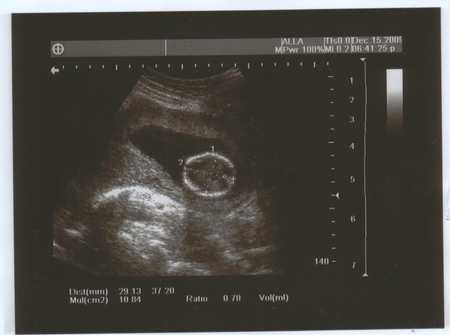

Даже в сегодняшнем гороскопе на ББ написано, что у меня целый день будет блаженное настроение до самого вечера! Ладно, ближе к теме)))) Кароче, пришла я на УЗИ, живот намазали, и тетя-врач в монитор смотрит и говорит, что малыш большой, здоровый, всё на месте, на неделю больше своего срока, то есть, срок по месячным у меня 14 недель и 4 дня, а по УЗИ 15 недель и 4 дня!))) о как!!! Богатырь или богатырша!!!! Переднее предлежание плаценты.. или чего-то там... КТР - 95 мм.Сказала, что у меня все отлично, ни тонуса, ни чего-то ещё.. все в порядке))) Потом повернула монитор и я увидела своего малыша. Она мне ласково начала рассказывать, где ножки, ручки.. да я и сама все видела!!!! Это на фотках плохо видно, а в живую, когда он шевелится - отлично. Я видела всё!!! Он мне и махал и палец сосал!))) Действительно, было состояние блаженства. Я только охала и ахала, просто удивлялась.. не ужели.. этот живой малыш у меня в животе?!)))) Вот и малыш и вопрос, что на 3-й фотографии??? Мы с мужем не поняли))) кто знает, напишите, пожалуйста!)))

здорово! на третьей фотке похоже головка сверху и там разметки такие это размер головки меряли)) я тоже делала узи, на 17 недели, мне тоже ставили на неделю больше срока, и сказали что похоже на девочку)) фото получилось очень отчетливое, смотрю и любуюсь)) так приятно...